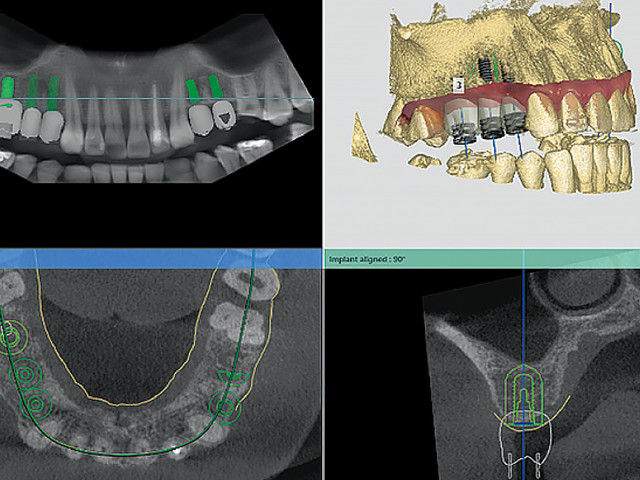

3D CT 정확한 진단 및 시술 계획

임플란트CT 촬영 및 3D 구강 스캐닝을 통해

환자의 턱뼈 구조, 신경 위치, 잇몸 상태 등을 정밀하게 분석하여 최적의 임플란트 위치와 각도를 결정합니다.

가상 모의 수술

임플란트 완성도는 높이고, 정확하고 빠른 임플란트 수술 3D 정밀진단을 바탕으로 실제 수술 전에 가상 모의수술을 통해 임플란트의 위치 및 깊이, 그리고 신경 손상 등 사전 모든 위험요소를 차단하여, 최적의 임플란트 식립 위치를 결정합니다. 이를 통해 정확성과 안전성을 높이고, 수술 결과를 미리 예측할 수 있습니다.

ROYCE IMPLANT

임플란트 완성도는 높이고, 정확하고 빠른 임플란트 수술

3D 정밀진단을 바탕으로 실제 수술 전에 가상 모의수술을 통해

임플란트의 위치 및 깊이, 그리고 신경 손상 등 사전 모든 위험요소를 차단하여, 최적의 임플란트 식립 위치를 결정합니다. 이를 통해 정확성과 안전성을 높이고, 수술 결과를 미리 예측할 수 있습니다.

모의수술

정밀성과 안전성을 높이며, 치료 성공률을 극대화 합니다.

임플란트 치료를 위해 진행되는 모의 가상수술은 컴퓨터 시뮬레이션 기술을 활용하여 정밀한 치료 계획을 세우는 과정입니다.

3D CT 촬영으로 얻은 데이터를 기반으로 환자의 뼈 구조, 신경 위치, 잇몸 상태를 시각적으로 분석하며, 임플란트의 최적의 위치, 각도, 깊이를

찾아 시뮬레이션 합니다 .

디지털 가이드를 설계하여 수술 중 오차를 최소화하고, 예측 가능한 치료 결과를

제공합니다.